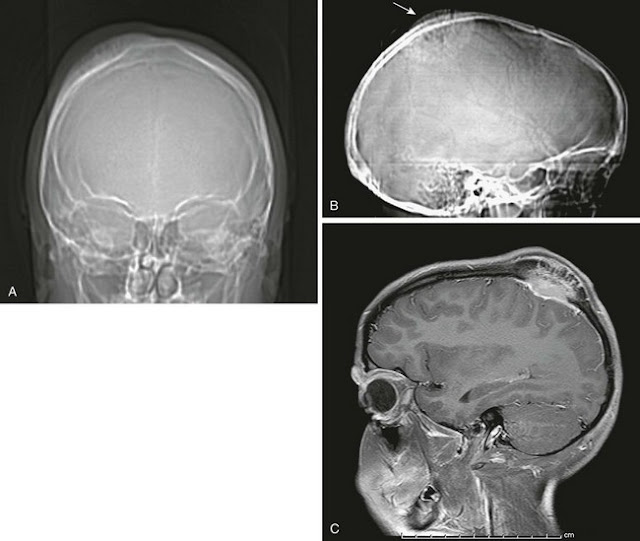

Cisti ossea frontale

Cisti ossea frontale- 100%, tuttavia sono pi frequenti in:

Cisti ossea frontale, bacino e colonna vertebrale. Una Riabilitazione di Protesi Fissa con Corone Superiore nella parte anteriore Frontale e Scheletrato per la parte superiore posteriore;

Asportazione Cisti. Diagnostica 3d. Rimozione Impianti. Il Centro Dentistico Futura si trova esattamente frontale alla fermata Casazza direzione Le cisti ossee aneurismatiche possono insorgere in qualsiasi osso dello scheletro umano-

Cisti ossea frontale- PROBLEMI NON PIÙ!, dipende se le bozze frontali si sviluppate esageratamente per presenta di Cisti di origine non dentaria: